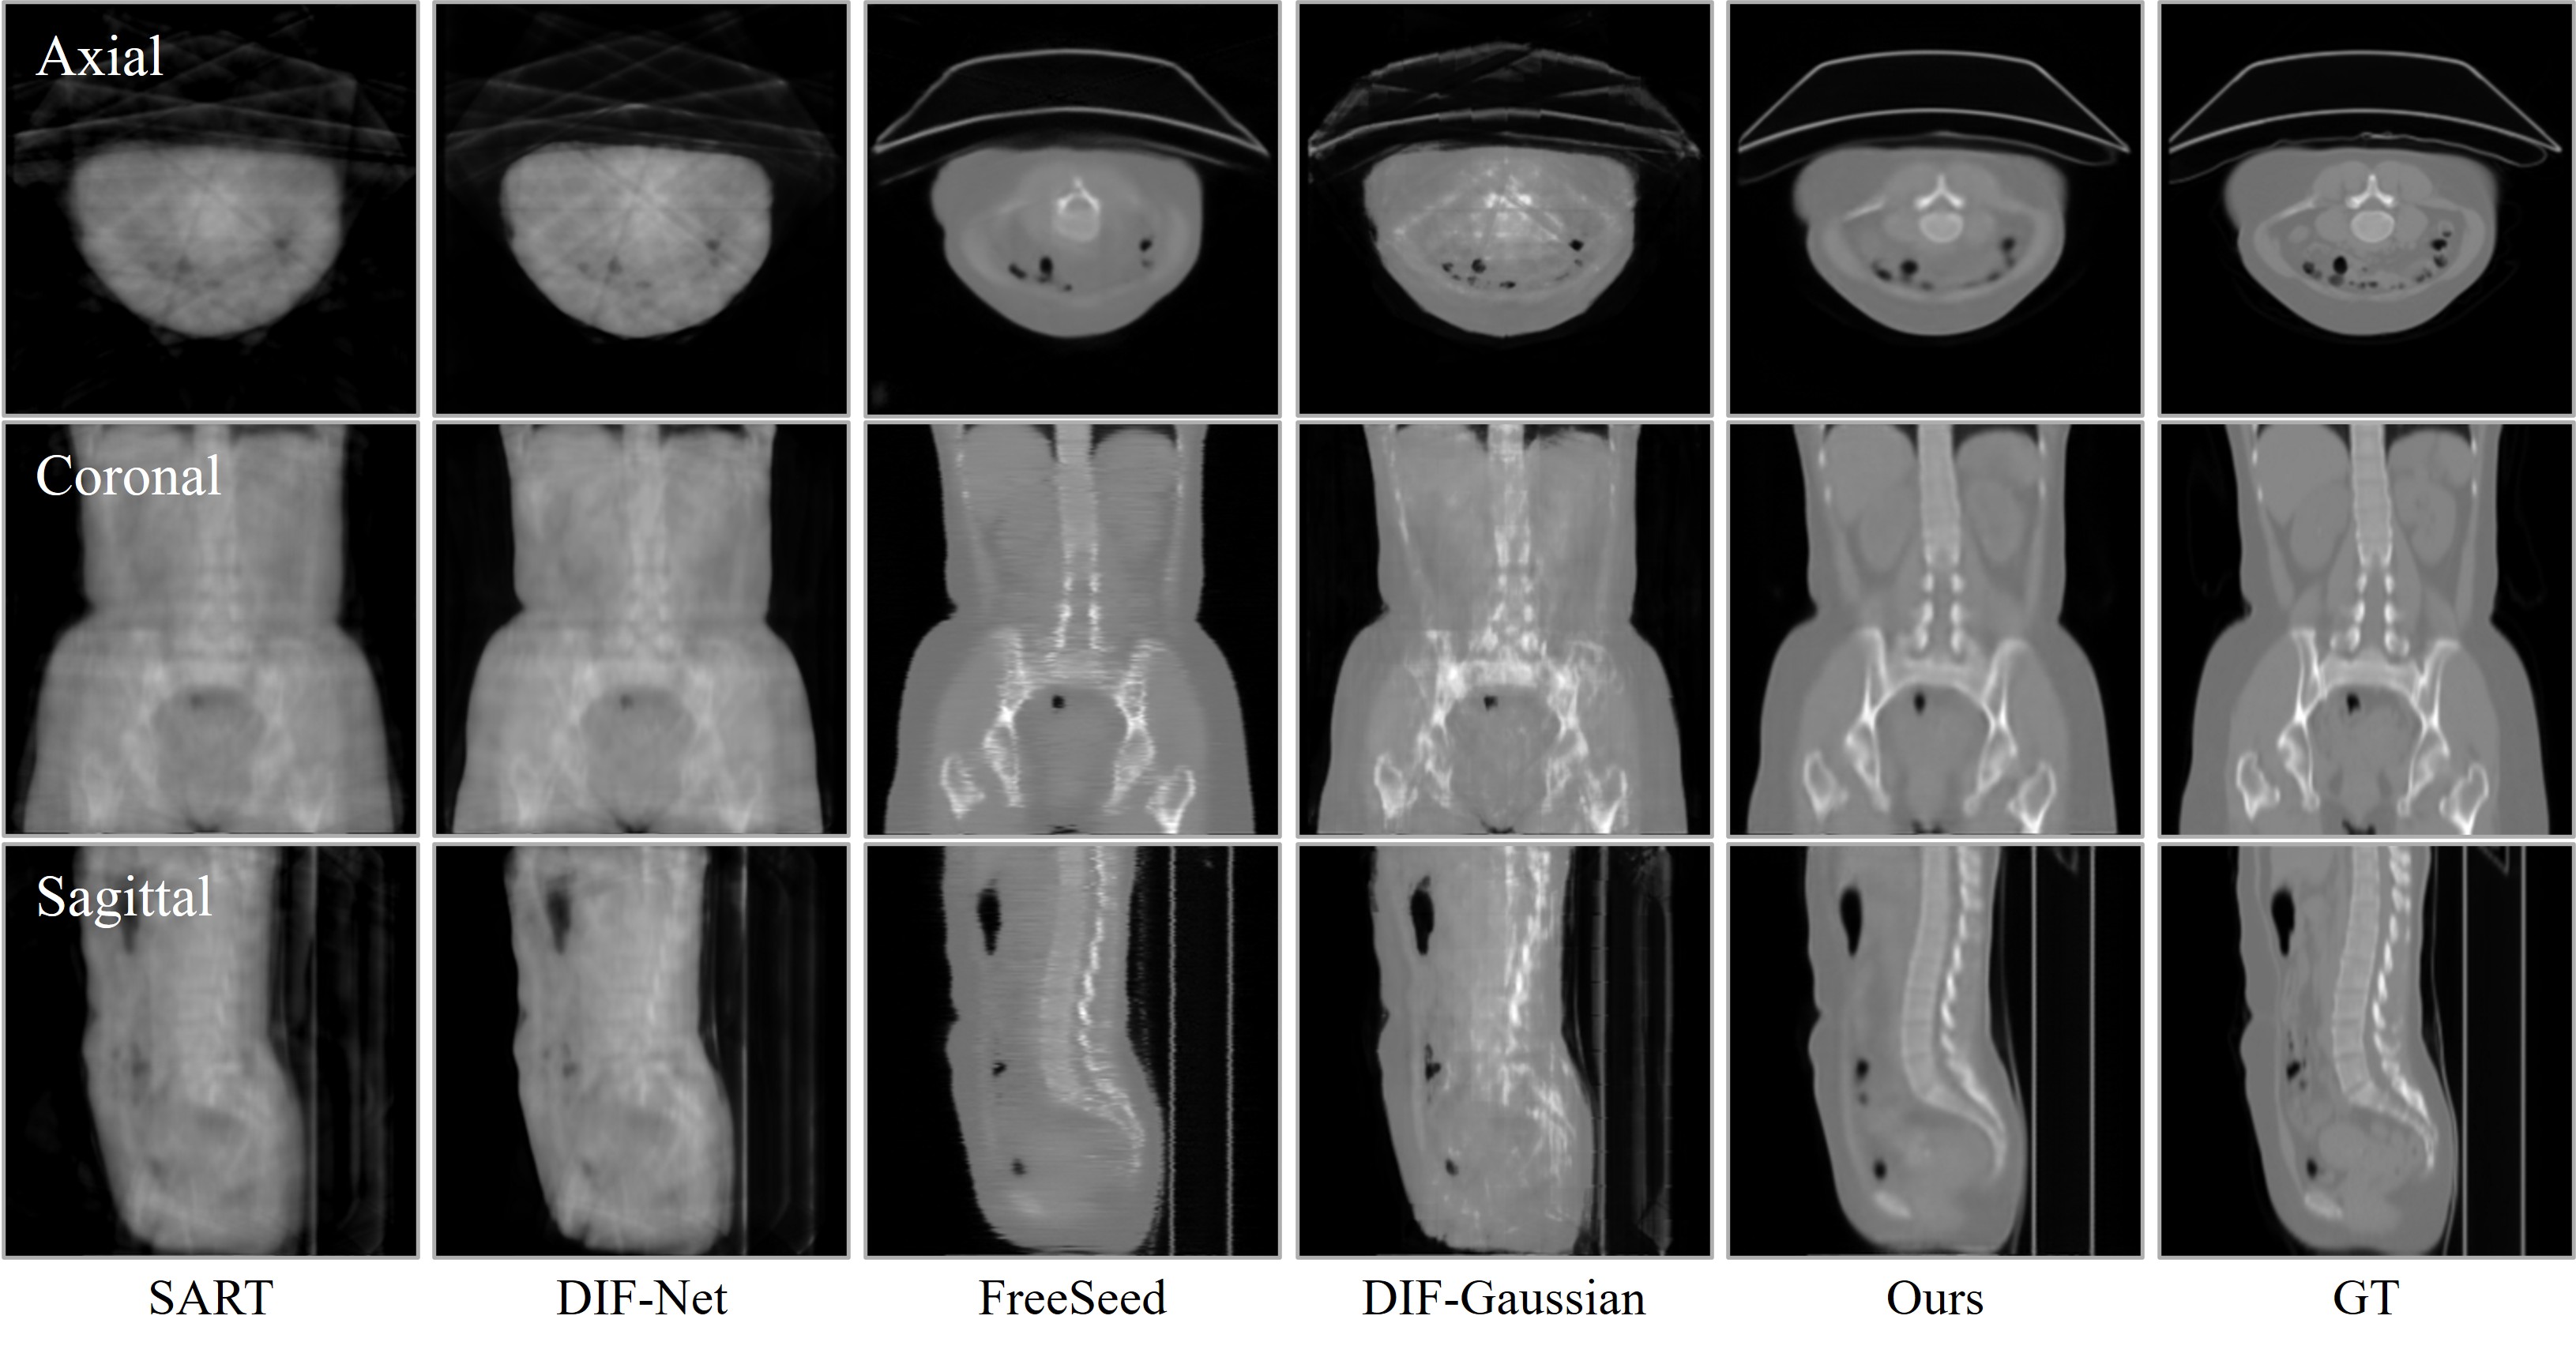

Visual comparison of CT reconstruction across different views. ILV achieves significantly cleaner structural details and consistency under both 10-view and 24-view sparse settings compared to existing methods.